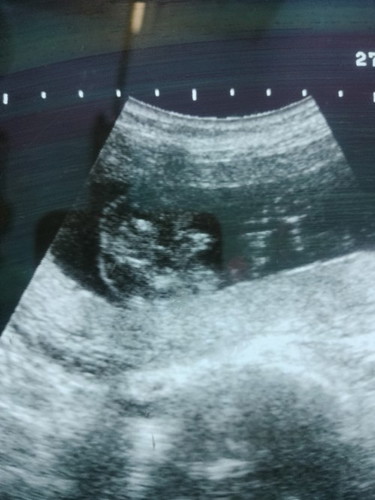

29สิงหาค่ะ 27มีนา หมอนัดไปดูเพศ อิแม่ตื่นเต้นหมอบอก น้องหลับค่ะคุณแม่ 24เมษาหมอนัดอีกทีค่ะ ลุ้นค่ะอิพ่ออยากได้ลูกสาว

ของแม่ๆชายหรือหญิงค่ะ